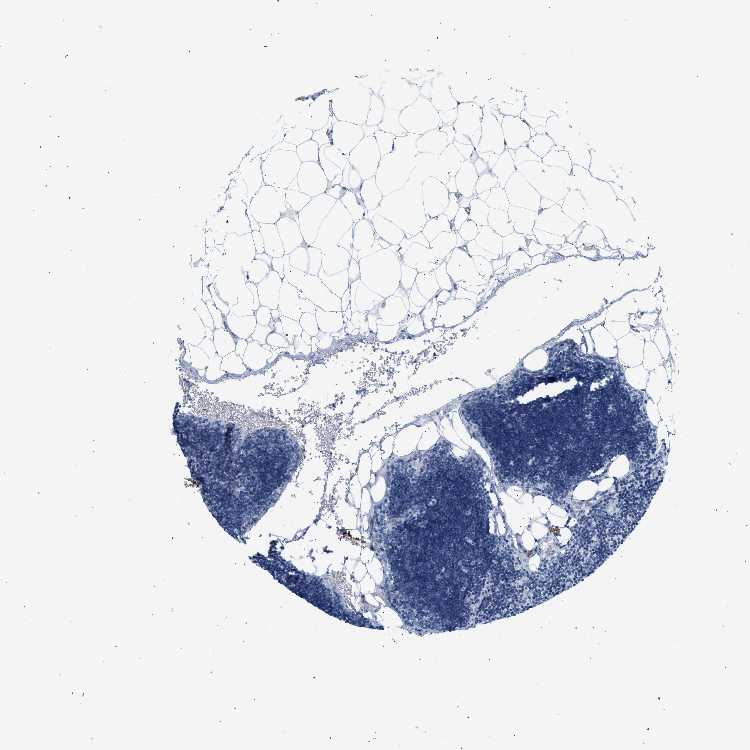

Information about each individual sample is listed below, including gender, age, a tissue section image and estimated fractions of cell types. nTPM (normalized transcripts per million) values give a quantification of the gene abundance which is comparable between different genes and samples.

Male, age 34

Lymph node sample 173

nTPM: 15.4

Cell types%

Lymphocytes:

85

Other cell types:

15